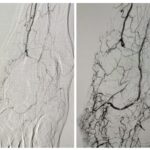

Caso clínico: Revascularización dirigida de un pie diabético complejo